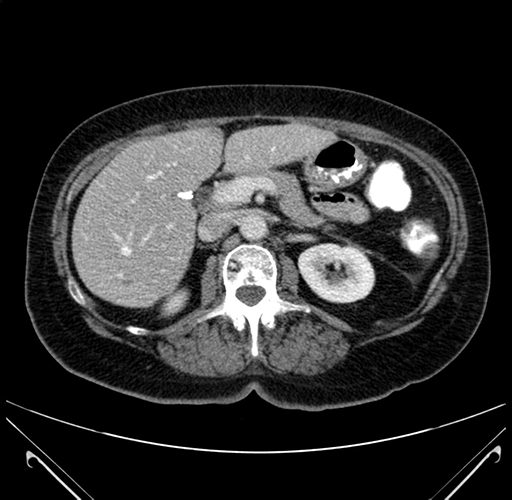

Axial Venous

Coronal Venous